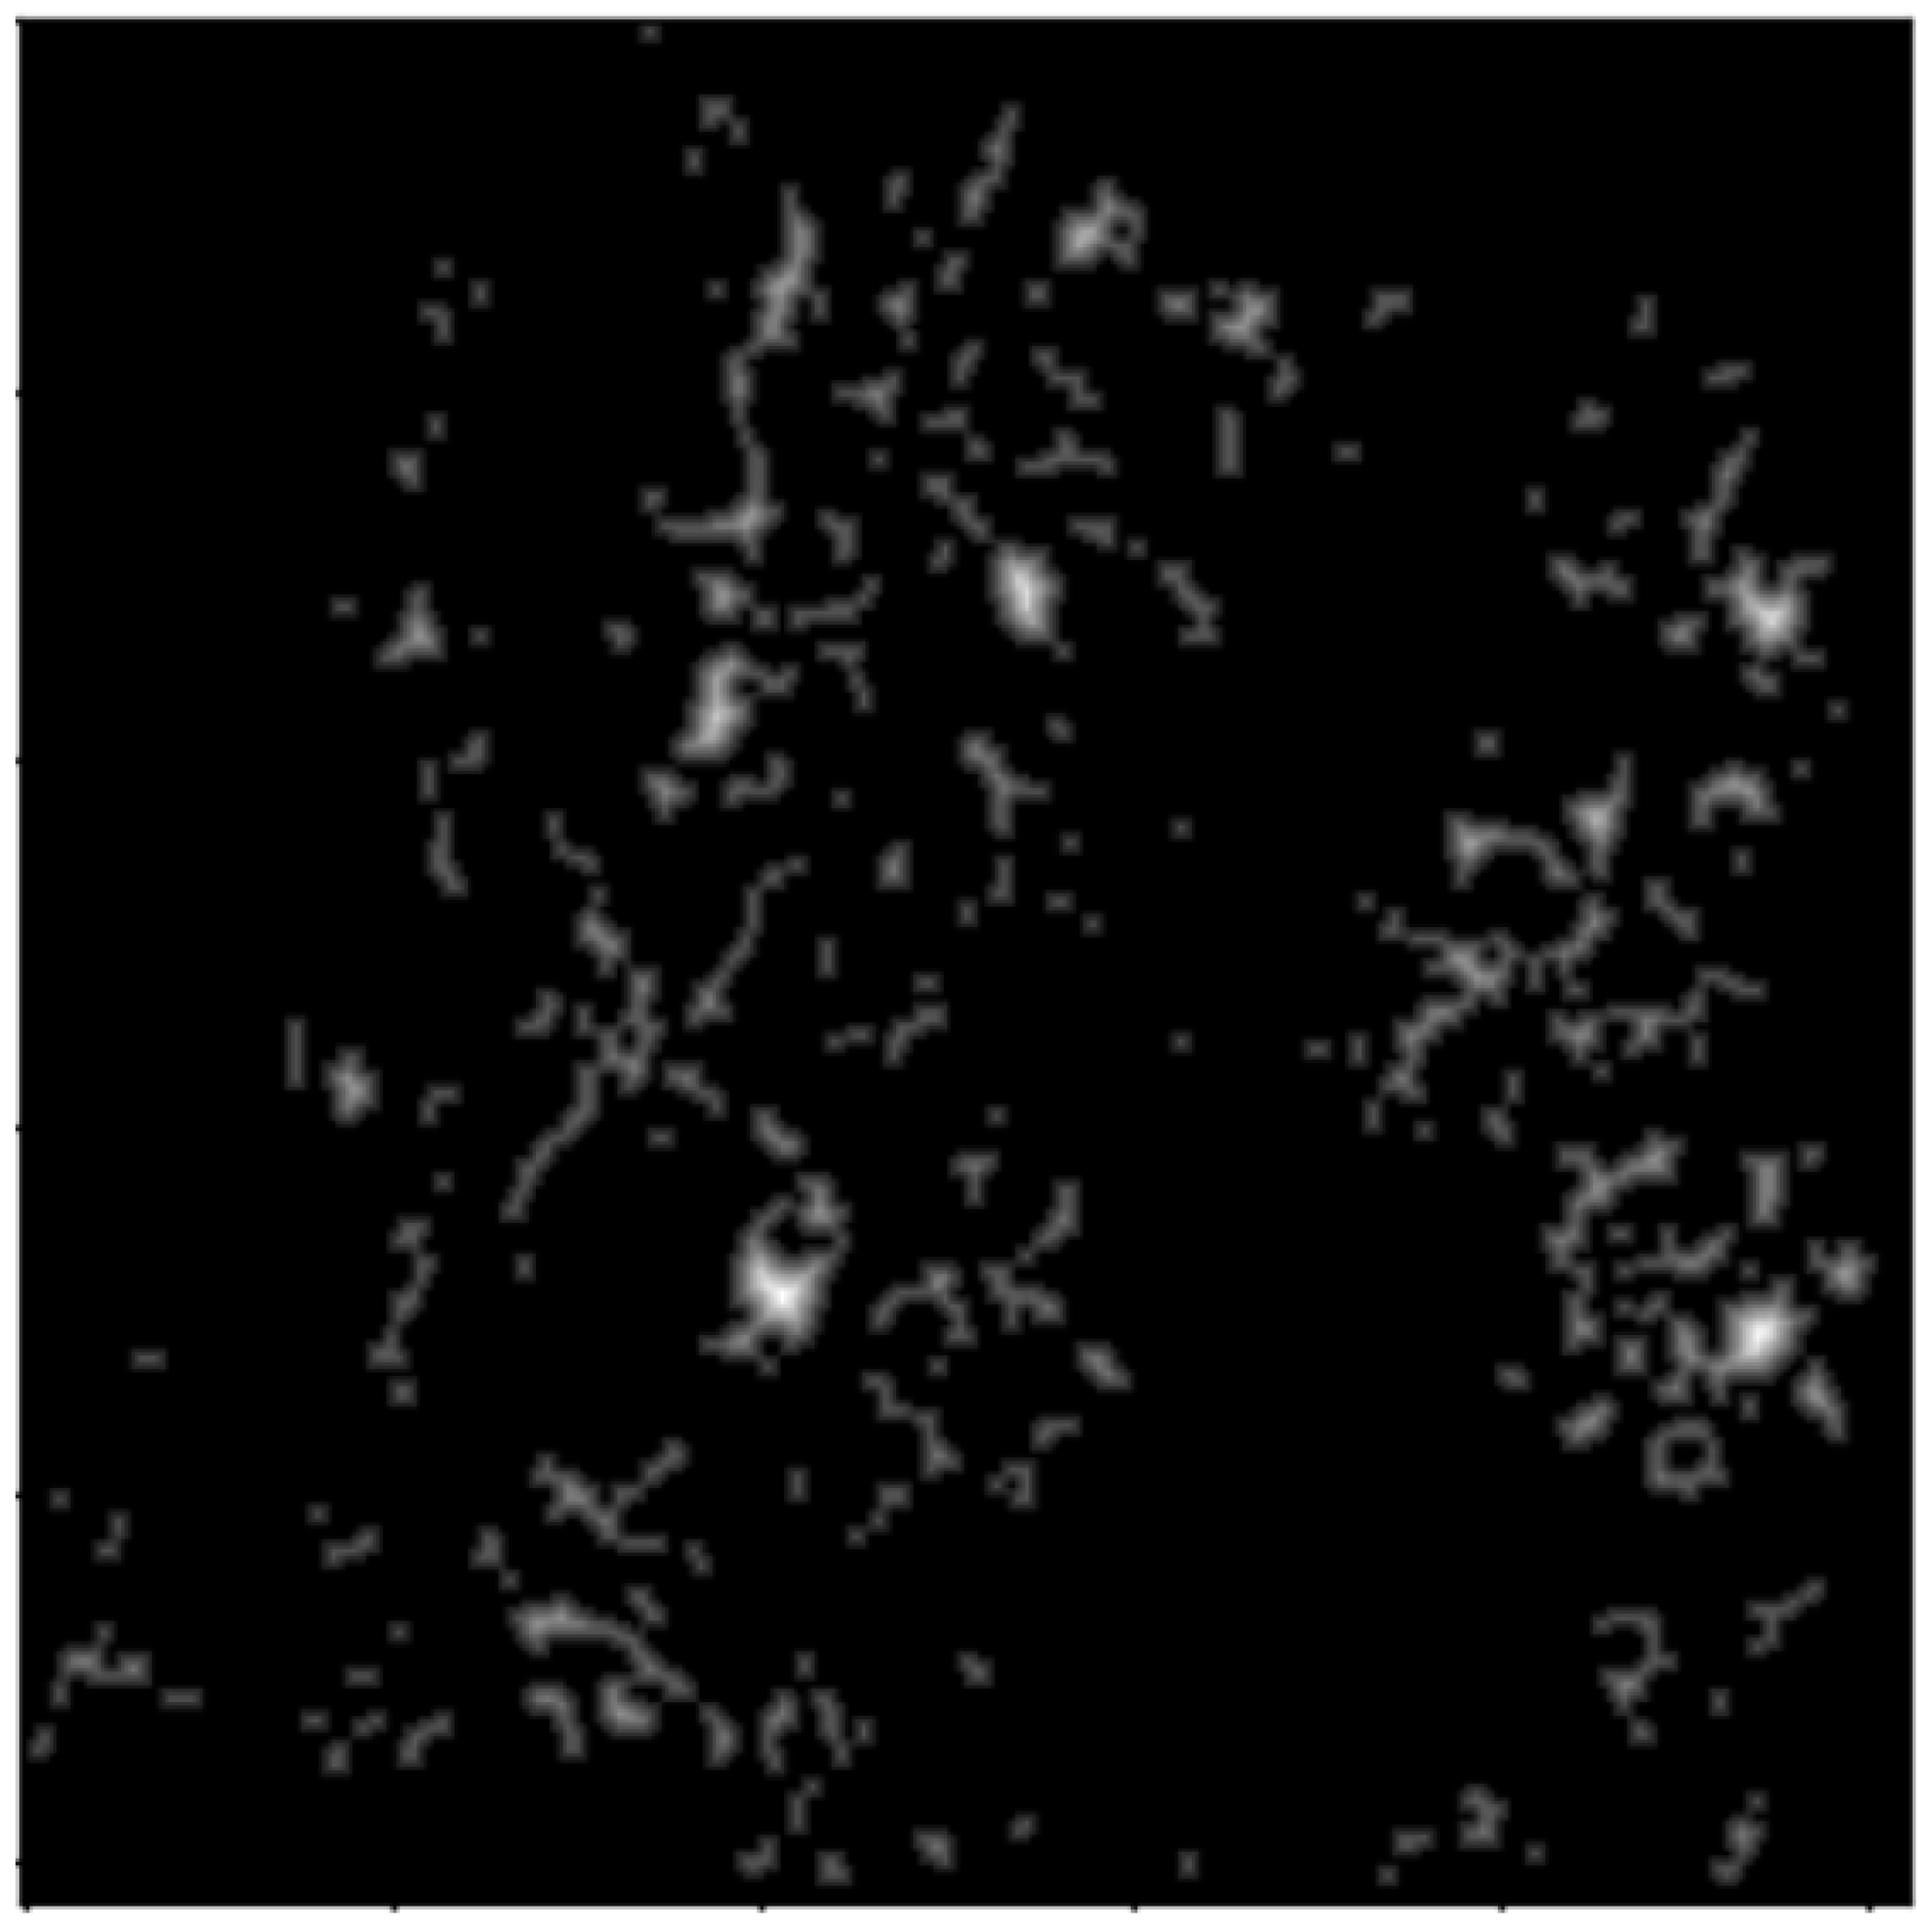

2.2.3. Distance Transform